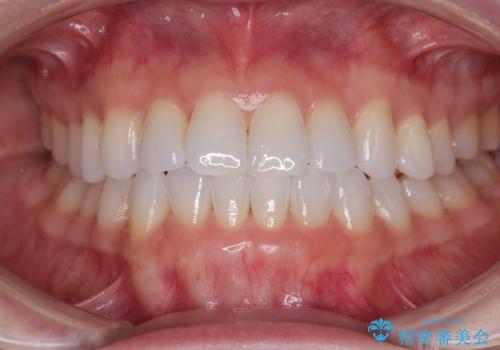

前歯のデコボコをインビザラインで綺麗に

- 上下前歯の叢生を気にして来院された患者様です。

インビザラインでの治療を希望されていて、デコボコの程度が中等度であり、安価なパッケージにて対応可能と判断されたため、インビザライン・モデレートを用いて矯正治療を行うこととしました。

インビザライン・モデレートは、製作できるアライナーの枚数に制限があるため、移動可能な量に限りがあるものの、インビザライン・ライトよりも枚数が多いため、幅広い症例に対応可能です。